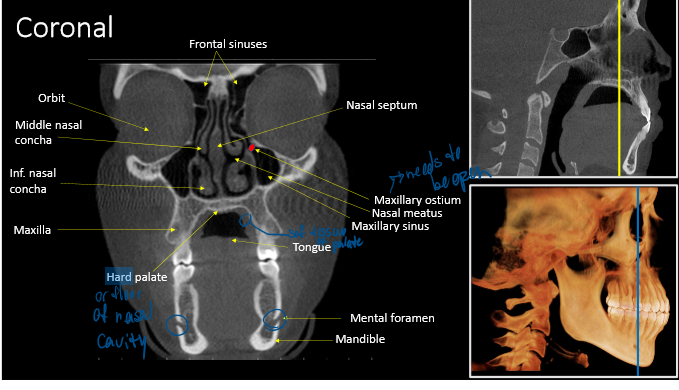

r. max sinus

mental foramen

hard palate

anterior nasal spine

lateral fossa

maxillary sinus

coronoid process